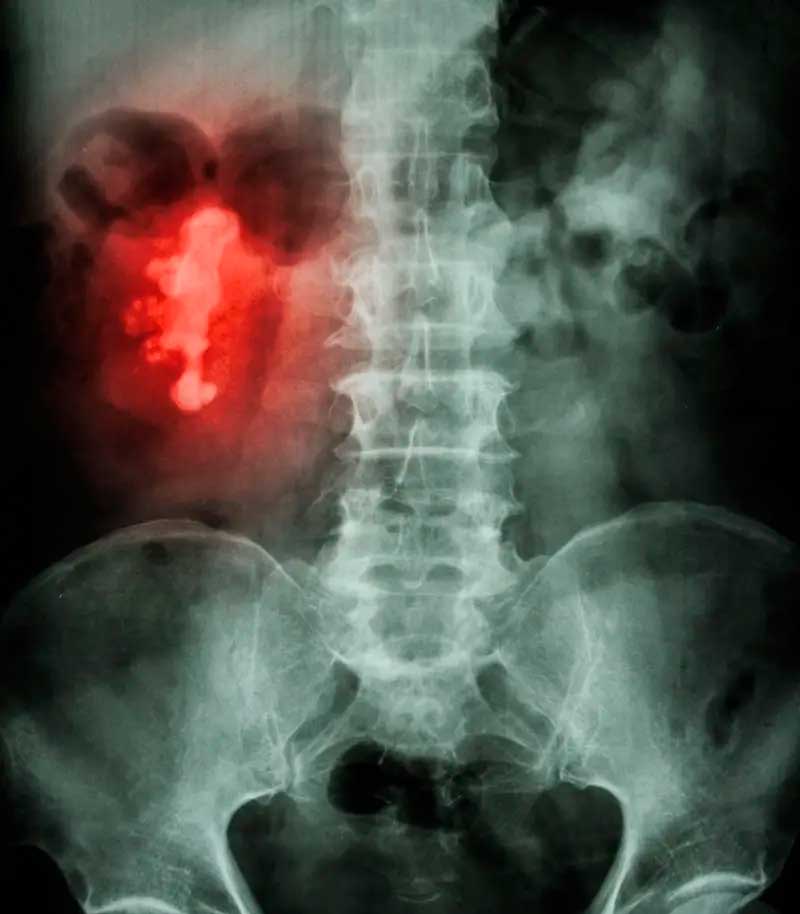

Los cálculos renales pueden variar considerablemente en tamaño, desde menos de un milímetro de ancho hasta centímetros o más . También pueden adoptar formas inusuales: si el cálculo se acumula dentro de los canales ramificados (cálices) del riñón, puede adoptar la forma de una cornamenta de ciervo. Esto se llama cálculo cuerno de ciervo .